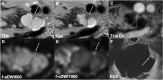

Methods: Eighty-two patients with known or suspected IPMN were retrospectively enrolled. Computed high-b-value images at b = 1000 s/mm2 were calculated from standard (b = 0, 50, 300, and 600 s/mm2) DWI images for conventional full field-of-view (fFOV, 3 × 3 × 4 mm3 voxel size) DWI. A subset of 39 patients received additional high-resolution reduced-field-of-view (rFOV, 2.5 × 2.5 × 3 mm3 voxel size) DWI. In this cohort, rFOV cDWI was compared against fFOV cDWI additionally. Two experienced radiologists evaluated (Likert scale 1-4) image quality (overall image quality, lesion detection and delineation, fluid suppression within the lesion). In addition, quantitative image parameters (apparent signal-to-noise ratio (aSNR), apparent contrast-to-noise ratio (aCNR), contrast ratio (CR)) were assessed. Diagnostic confidence regarding the presence/absence of diffusion-restricted solid nodules was assessed in an additional reader study.

Results: High-b-value cDWI at b = 1000 s/mm2 outperformed acquired DWI at b = 600 s/mm2 regarding lesion detection, fluid suppression, aCNR, CR, and lesion classification (p = < .001-.002). Comparing cDWI from fFOV and rFOV revealed higher image quality in high-resolution rFOV-DWI compared to conventional fFOV-DWI (p ≤ .001-.018). High-b-value cDWI images were rated non-inferior to directly acquired high-b-value DWI images (p = .095-.655).